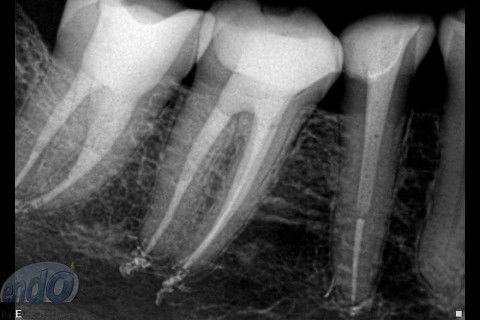

Tratamento Endodôntico dos Dentes 45 - 46 - 47

Seguem 3 casos clínicos realizados esta semana em uma cliente que está passando por um tratamento estético. O dente 47 apresentava calcificação da entradas dos canais radiculares, provavelmente, devido a uma pulpotomia realizada no passado. Desta forma, foi dedicada uma consulta de aproximadamente 2 horas para a realização deste procedimento. Os dente 45 e 46, por apresentarem canais radiculares com menor complexidade, foram tratados, simultaneamente, em sessão única com duração de aproximadamente 2 horas e 15 minutos.

Os três dentes foram tratados seguindo a técnica da FOP-UNICAMP, na qual é realizada patência e ampliação do forame apical. A instrumentação foi realizada com instrumentos rotatórios e como substância química auxiliar foram utilizados o ENDOGEL e o EDTA 17%. A irrigação ativa foi realizada com soro fisiológico. Os canais foram obturados com guta-percha e cimento PulpCanal Sealer, pela técnica de ondas contínuas de condensação.

Os procedimentos pré-restauradores nos dentes 46 e 47 envolveram apenas a confecção de núcleo de preenchimento em resina composta (Z250 B0,5). No dente 45 foi instalado um pino de fibra de vidro (FGM) e confeccionado núcleo de preenchimento em resina composta (Z250 B0,5).